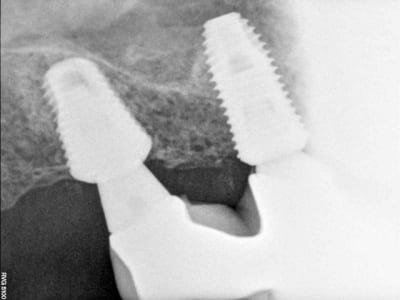

comme ce petit cas

la 2ème radio est prise 18 mois après la 1ère

PS pour Gulguch c'est bien un implant de 6 mm de diamètre en distal et pourtant pas la moindre perte osseuse...